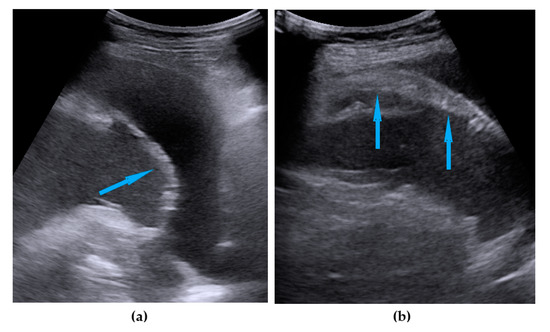

| Frozen pelvis | Massive pelvic involvement: hypoechogenic tissue in the peritoneum in the pouch of Douglas, forming cohesion between ovarian masses, bowel, uterus, and posterior pelvic wall. It manifests in the dynamic ultrasound examination: absence of sliding sign between the rectum and uterus/ovaries and between the uterus, urinary bladder, and pelvic walls. | Figure 12 | Video S12 |

| Rectum-sigmoid | Suspected involvement of the rectosigmoid wall manifests as the presence of metastases over the wall of the rectum or sigmoid. | Figure 13 | Video S13 |